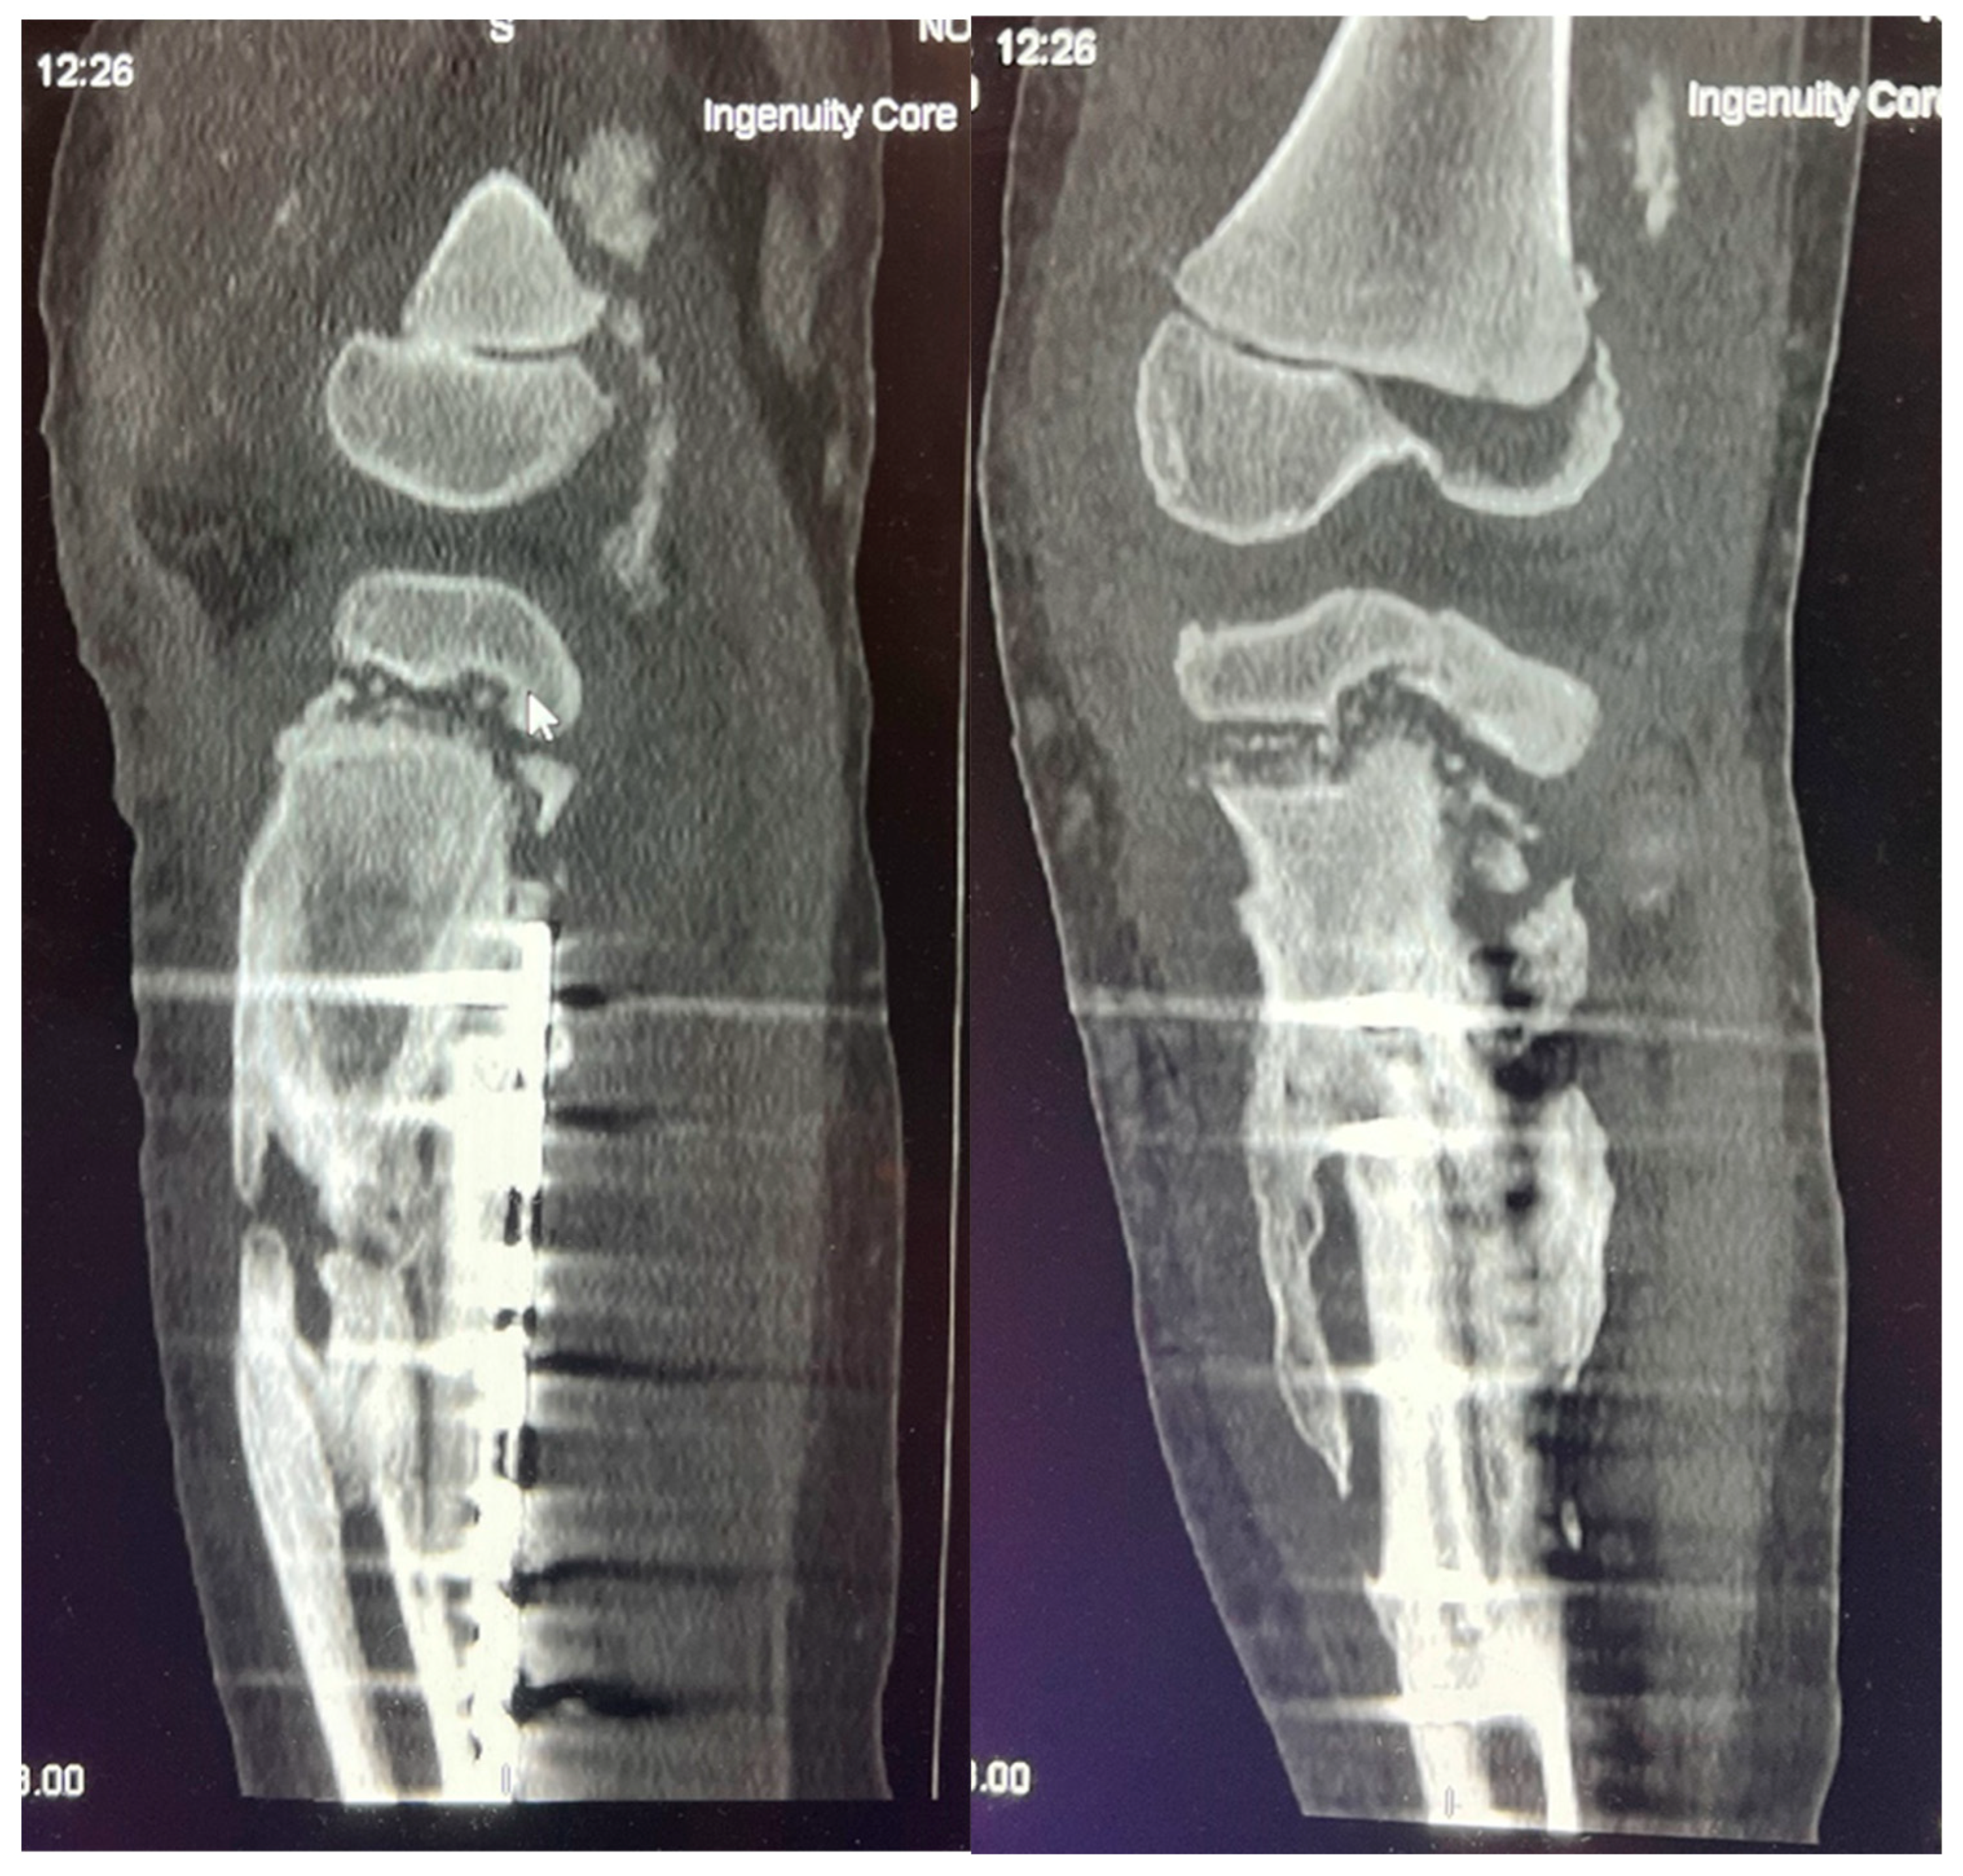

She developed septic symptoms and was admitted to a hospital in Dublin, Ireland, where repeated interventions were done to drain the excess fluid. She also received antibacterial therapy (Rifampicin and Cefazolin). Radiological examinations were performed (X-ray, CT, magnetic resonance imaging (MRI)), showing extensive changes from the distal third of the thigh to the distal third of the calf. The inflammatory process was visible in the distal femur and proximal tibial growth zone. Wide areas of destruction were also observed, which included the ossifications forming around the left knee joint. Formation of massive ossification around the diaphysis of the tibia with no signs of convalescence in the bone itself (Figure 8 and Figure 9). MRI examination of the left knee was performed due to knee joint effusion, where an abnormal amount of fluid in the joint and signs of inflammation were determined.

Figure 9. CT imaging shows an inflammatory process in the distal femur and proximal tibial growth zone, with wide areas of destruction, including the left knee joint bones, and massive ossification around the tibia diaphysis, without signs of convalescence.